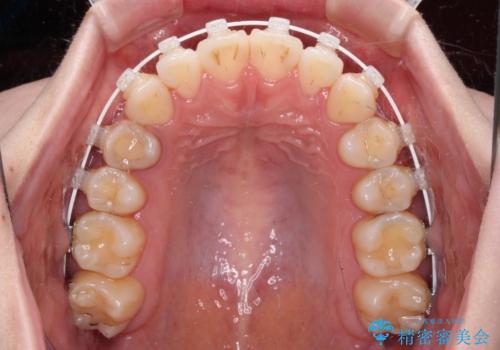

舌突出癖による開咬 舌のトレーニングを行いながら前歯の隙間を改善

- 上下前歯の隙間を気にして来院された患者様です。

前歯が、舌の突出癖により上下前歯が非接触となっている状態でした。

上下前歯が非接触である開咬は、インビザラインによる治療がお勧めではありますが、しっかりと使う自信がないとのことで、ワイヤー装置にて治療を行うこととしました。

ワイヤー矯正での開咬改善には時間がかかります。

舌の突出癖改善のトレーニングをしっかりと行っていただき、上下前歯が接触する咬み合わせを達成することができました。